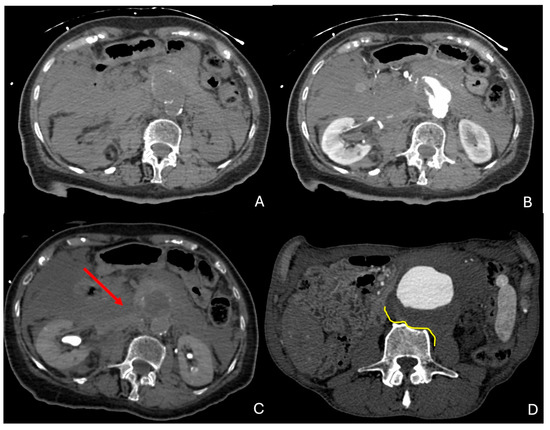

3. CTA Findings of Aneurysm Rupture

- Rakita, D.; Newatia, A.; Hines, J.J.; Siegel, D.N.; Friedman, B. Spectrum of CT Findings in Rupture and Impending Rupture of Abdominal Aortic Aneurysms. RadioGraphics 2007, 27, 497–507. [Google Scholar] [CrossRef]

- Schwartz, S.A.; Taljanovic, M.S.; Smyth, S.; O’Brien, M.J.; Rogers, L.F. CT Findings of Rupture, Impending Rupture, and Contained Rupture of Abdominal Aortic Aneurysms. Am. J. Roentgenol. 2007, 188, W57–W62. [Google Scholar] [CrossRef]